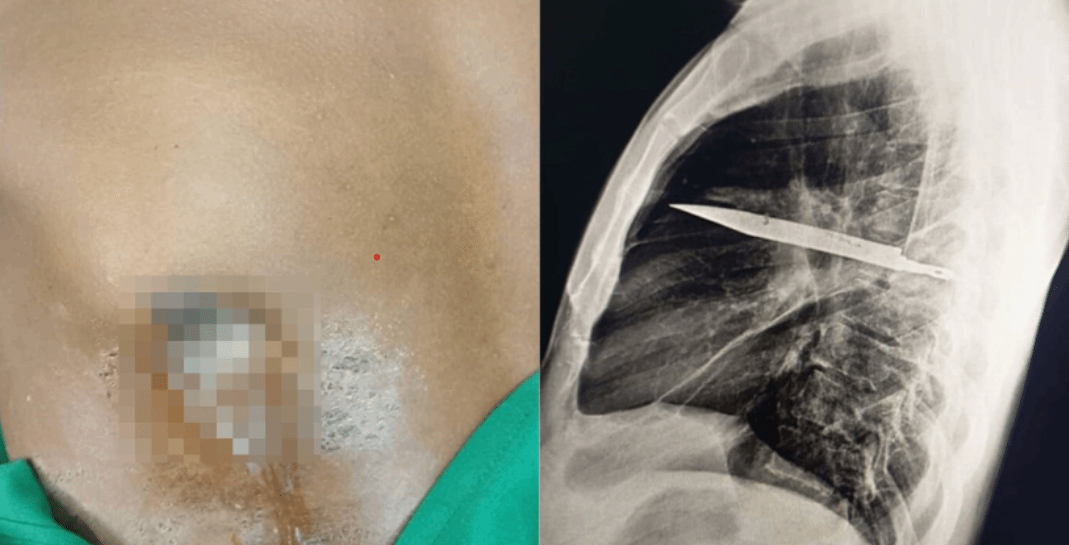

男子胸部流脓8年怪病难愈,一照X光吓一跳:体内竟藏着把刀